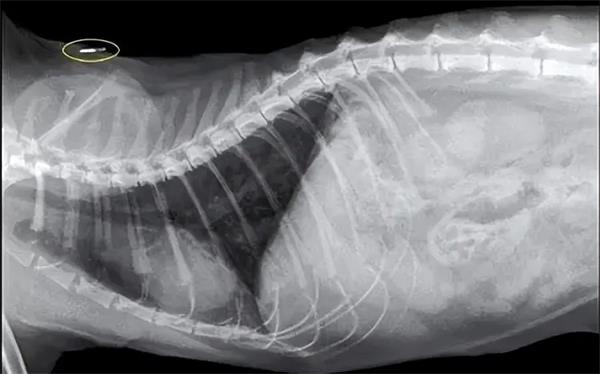

犬只芯片产品一般是指,宠物主在为犬只登记狗牌的同时为宠物狗注射内含低频RFID芯片的玻璃管。

植入犬只身体后的RFID标签(图源:网络)